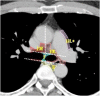

The purpose of this study was to develop a consensus-based computed tomographic (CT) atlas that defines lymph node stations in radiotherapy for lung cancer based on the lymph node map of the International Association for the Study of Lung Cancer (IASLC). A project group in the Japanese Radiation Oncology Study Group (JROSG) initially prepared a draft of the atlas in which lymph node Stations 1-11 were illustrated on axial CT images. Subsequently, a joint committee of the Japan Lung Cancer Society (JLCS) and the Japanese Society for Radiation Oncology (JASTRO) was formulated to revise this draft. The committee consisted of four radiation oncologists, four thoracic surgeons and three thoracic radiologists. The draft prepared by the JROSG project group was intensively reviewed and discussed at four meetings of the committee over several months. Finally, we proposed definitions for the regional lymph node stations and the consensus-based CT atlas. This atlas was approved by the Board of Directors of JLCS and JASTRO. This resulted in the first official CT atlas for defining regional lymph node stations in radiotherapy for lung cancer authorized by the JLCS and JASTRO. In conclusion, the JLCS-JASTRO consensus-based CT atlas, which conforms to the IASLC lymph node map, was established.